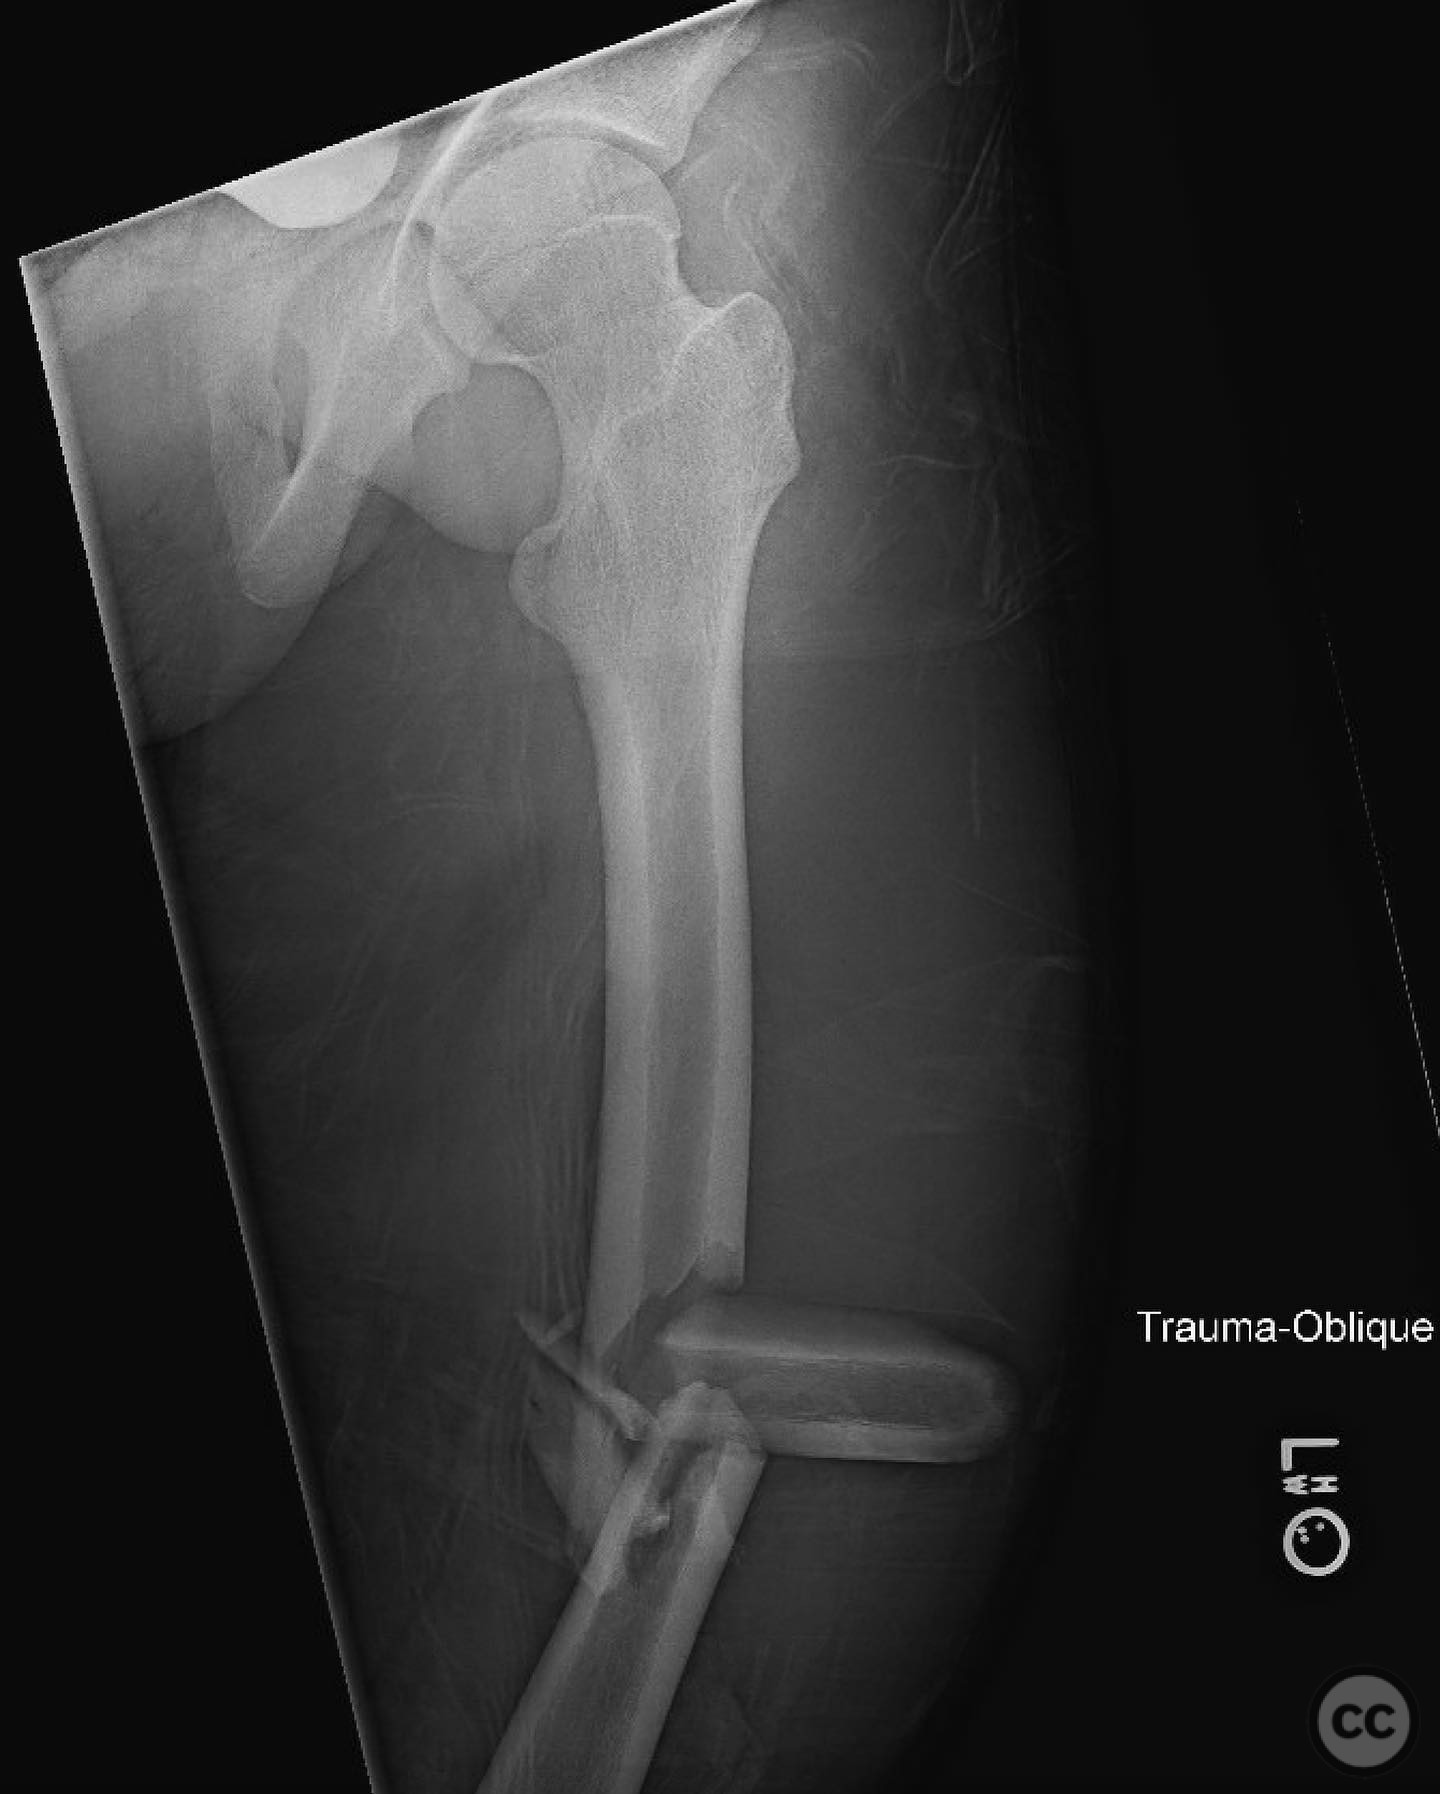

Comminuted Diaphyseal Femur Fracture in a 16-Year-Old

Clinical and radiological findings:  A 16-year-old male sustained a comminuted diaphyseal femur fracture after a 50-foot fall while rock climbing. The patient presented with multiple injuries but was well resuscitated and cleared for surgical treatment of the femur fracture within 24 hours. The injury was closed, with no neurological or vascular compromise noted.

Planning remarks:  The preoperative plan involved an open reduction and internal fixation (ORIF) due to the complexity of the fracture and the presence of a large incomplete napkin ring segment that could not be managed with closed nailing techniques. The anatomical approach was planned through a lateral incision to allow direct access to the fracture site for reduction and fixation.